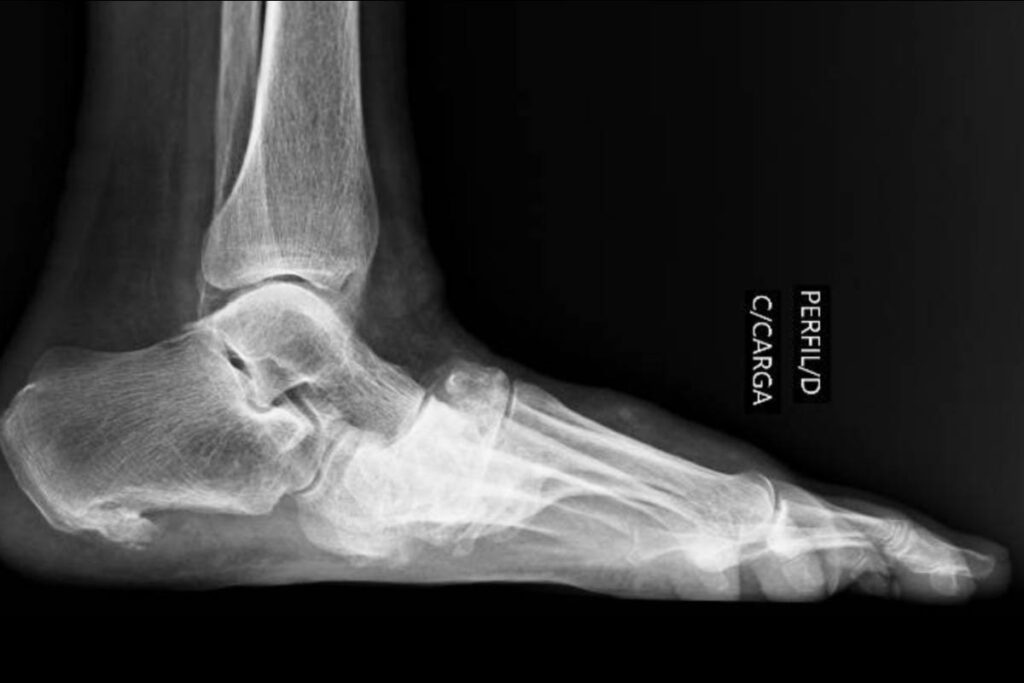

Imagens clínicas e de radiografias demonstrando um paciente com Artropatia de Charcot. Fonte: DOI: 10.1186/s13244-019-0768-9

Exemplo de artropatia de Charcot – Fraturas diversas em processo de consolidação nos óssos do médio-pé.

Os exames de imagem, como radiografias, tomografia computadorizada ou ressonância magnética, são usados para confirmar o diagnóstico e avaliar a extensão da condição. Estes podem mostrar alterações ósseas e articulares características da condição.